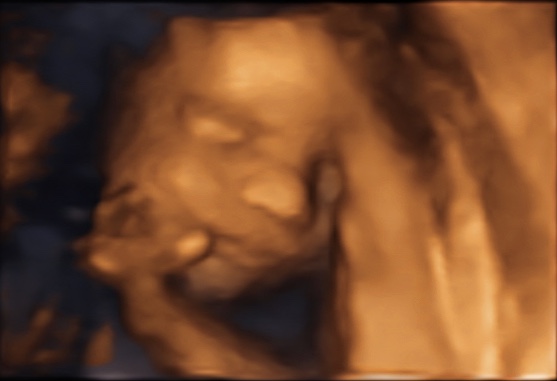

34 weken

Een echo na 34 weken.